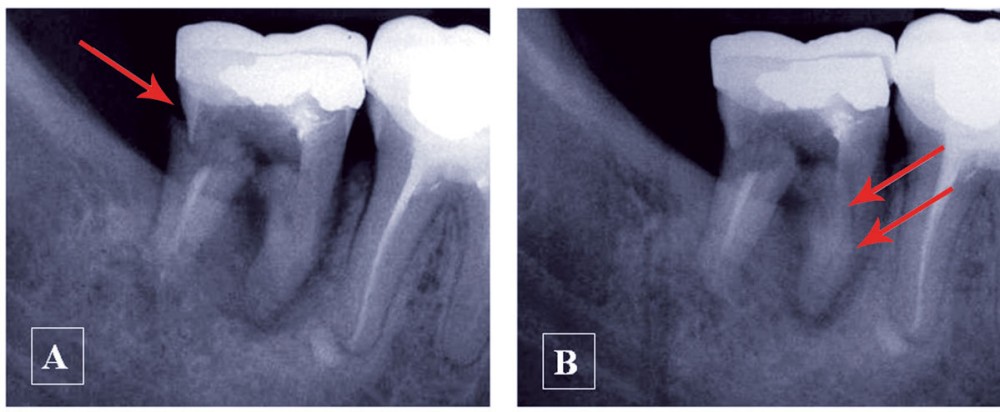

– pour sa forme suivant l’orthogonalité ou l’obliquité du rayonnement par rapport au récepteur (fig. 1).

Une structure anatomique n’est radiologiquement visible que si le rayon directeur (axe du faisceau Rx incident) est tangent à cette structure. Une fracture radiculaire longitudinale ne sera mise en évidence qu’aux conditions d’une orientation favorable et de dimensions suffisantes (fig. 2).